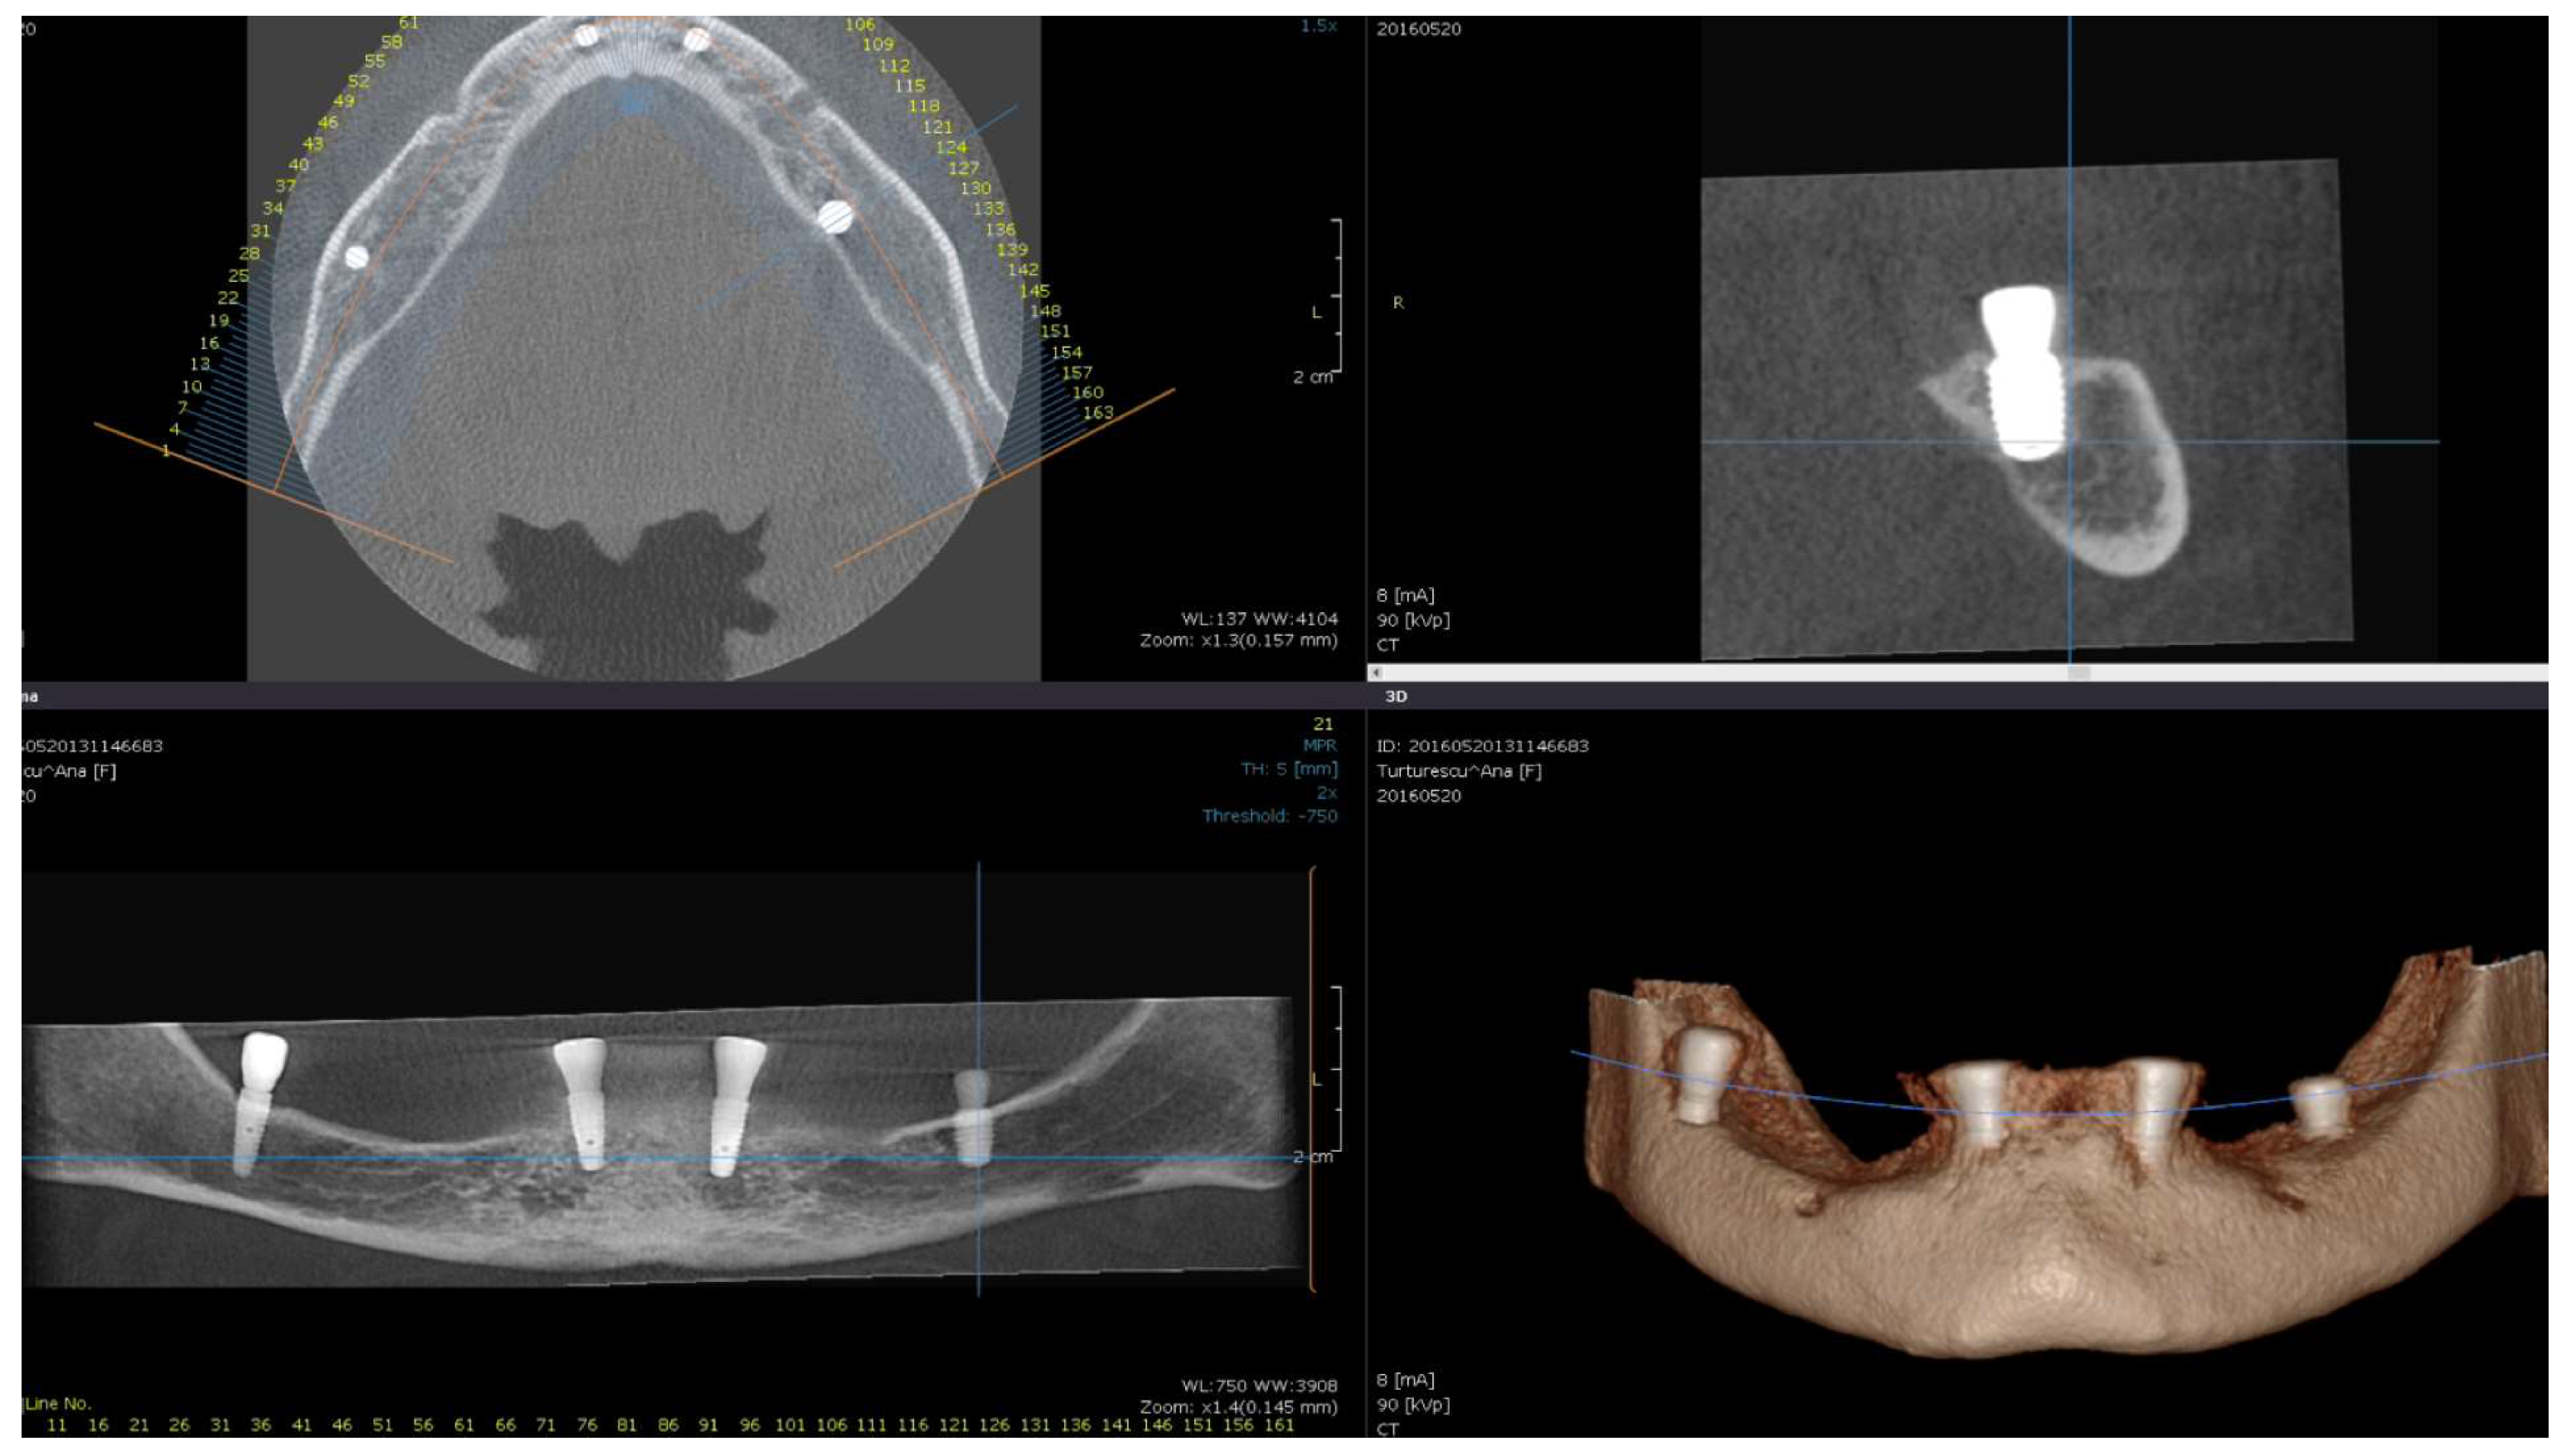

Direct visual access to the residual bone was obtained by elevating a full muco-periosteal flap. A lance drill was used to mark the implant site at approximately 2 mm towards the midcrest with respect to the buccal or lingual cortex. To avoid thermal osteonecrosis, copious cooling irrigation, new drills, and a maximum speed of 800 RPM were used for implant site preparation. After the osteotomy site was marked, a pilot 2 mm drill was selected to perform the preparation for the length of the selected implant. In-and-out manoeuvres were performed in order to facilitate cooling of the drills. If the implant is planned to be placed buccally, the drill must be oriented with the apex faced towards buccal wall, trying to keep the axis of the drill parallel to the buccal cortex. In most of the cases, if the pilot drill direction was properly assessed, minimal or even no bleeding will be observed and the patient will indicate no pain. If the osteotomy preparation was performed buccally, a bone dehiscence might be present. In this scenario, the following drills must be slightly pressed towards the inner wall (wall facing towards the middle of the alveolar crest) of the osteotomy site. This manoeuvre is performed by a digital propelling force on the head of the handpiece, according to the preparation protocol for D1 bone recommended by the implant company. If a 4.0 mm diameter tapered implant (AnyRidge, Megagen Implant Co., Daegu, Republic of Korea) is planned to be used, the following drills were selected for convenient site preparation: 2.7 mm, 3.3 mm, 3.8 mm for the whole length of the osteotomy and a 4.3 mm drill was used only for countersink. Implant insertion was done with the surgical motor (at 35 RPM). A similar drilling protocol is applied for 3.5 mm diameter implants (last drill 3.3 mm and 3.8 mm countersink) and a 4.3 mm drill for the whole length, for 4.5 mm diameter implants. Depending on the thickness of the surrounding soft tissues and the relation with the buccal mucosa, either a 7 mm long healing abutment (I-Gen Kit, Megagen, Daegu, Republic of Korea) or a customized healing abutment was connected to the implant, with digital clockwise rotations. Double layer suture (horizontal mattress and simple suture) was done with 5/0 resorbable suture (Vicryl, Ethicon, New Brunswick, NJ, USA). Patients were prescribed antibiotics (Augmentin®—amoxicillin plus clavulanic acid 1 g/every 12 h) and one tablet of anti-inflammatory drug (Ibuprofen 600 mg at every 8 h) for the following 5 days. Patients were instructed to avoid brushing the neighbouring teeth in the treated area and chlorhexidine solution (0.12%) was prescribed for daily usage (twice a day for 1 min). Sutures were removed after 14 days [16]. All patients were recalled for clinical checkup 1 day, 1 week, 2 weeks, and 2, 6, 12, 24, and 36 months after surgery. All complications, both during the surgery and postoperative, were reviewed. A postoperative CBCT was done to assess implant positioning. Buccally tilted and lingually tilted implant positioning are presented in Figure 1 and Figure 2, respectively.

Figure 1.

Postoperative CBCT of patient no. 6: (Upper left)—axial view of the mandible; (upper right)—sagittal left view of the buccally tilted implant (37); (lower left)—coronal view of the mandible; (lower right)—3D view of the mandible.